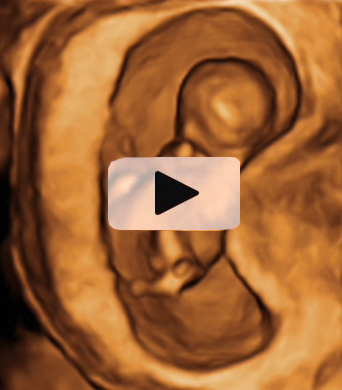

Diagnóstico de siameses de 11 semanas de gestación

Vemos la ecografía en dos dimensiones (2D) (figura A) de un corte transversal de los abdómenes de los fetos, a la altura del ombligo, mostrando la zona compartida (flechas). En la figura B, podemos observar la reconstrucción en 3D con la flecha señalando la zona compartida. Con los equipos ecográficos actuales este diagnóstico puede realizarse muy pronto. En este caso los gemelos están unidos por un puente fino a la altura de los cordones umbilicales y comparten una parte pequeña de hígado. Por suerte, la separación quirúrgica puede realizarse sin grandes dificultades.